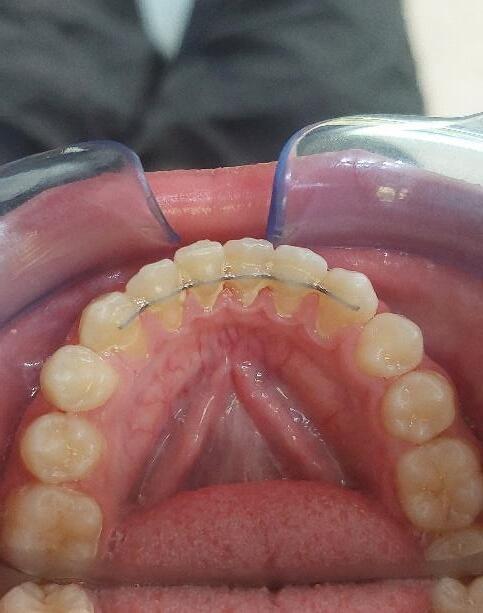

Γ4. Ελεγχος ανατολής κυνοδόντων και διάνοιξη υπερώας (ref.15,16)

Στα 7 χρόνια του παιδιού εξετάζουμε με πανοραμική ακτινογραφία τη θέση των μονίμων άνω κυνοδόντων στο οστό και αναλόγως πράττουμε.

Αν δεν υπάρχει αρκετός χώρος για αυτά,κάνουμε διεύρυνση της υπερώας με ορθοπεδικό μηχάνημα.

024 Με

να ανατείλουν και έτσι αποφεύγουμε μελλοντικό εγκλεισμό τους στο οστό της άνω γνάθου. Έγκλειστος κυνόδοντας σε ενήλικα, παρουσία του νεογιλού προγόνου του. Η σημασία της στοματικής υγιεινής και ορθοδοντικής πρόληψης

τον τρόπο αυτό τα βοηθάμε

Ορθοδοντική παρέμβαση στον συγκεκριμένο ενήλικα, μετά από χειρουργική αποκάλυψη του εγκλείστου κυνόδοντα, και μεταφορά του στο οδοντικό τόξο.

Για αποφυγή της παραπάνω διαδικασίας τονίζεται ξανά η σημασία του έγκαιρου ορθοδοντικού ελέγχου στην σχολική ηλικία των παιδιών για τη διάγνωση